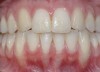

CASE 1 Fig 2. Pre-treatment clinical view of a 28-year-old patient with Miller Class I recession of the lower left central incisor treated with conservative SPT.

Figure 2

Fig 3. Two-year follow-up of same patient shows spontaneous root coverage.

Figure 3

When the tooth is properly aligned within the arch, treatment is managed with reference to Miller’s classification.7 Because most post-orthodontic GR cases are classified as Miller Class I and II defects, the authors focus on the management of these two classes only, and within the scope of this article, Miller Class III and IV defects are not addressed. Surgical root coverage of both Miller Class I and II defects is one treatment choice. However, in Miller Class I cases, a conservative approach can be considered, as well. Such an approach consists of supportive periodontal treatment (SPT)—professional periodic deposit removal every 2 to 3 months during a 1- to 2-year period. The authors’ clinical experience shows that spontaneous root coverage may occur following this conservative approach, particularly in young patients (Figure 2 and Figure 3). Similar results have been reported in a 3-year prospective study in which recession defects healed spontaneously following improvement in oral hygiene standards in children.30 In cases in which no root coverage is observed at the end of the follow-up period, surgical root coverage can be considered.